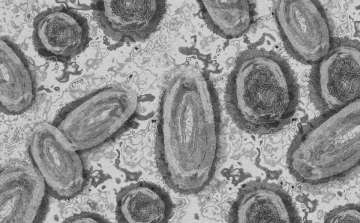

Tovább nőtt a majomhimlő-fertőzöttek száma Magyarországon

Újabb két embernél igazolt majomhimlő-fertőzést a Nemzeti Népegészségügyi Központ (NNK) a 33. héten - augusztus 15-től 21-ig -, ezzel 64-re nőtt a magyarországi esetek száma.

Meghaladta a 13 ezret a majomhimlő-fertőzöttek száma az Egyesült Államokban, a legtöbb esetet Kaliforniában és New York államban regisztrálták.

Megfertőződött majomhimlővel egy négyéves kislány Németországban - jelentették kedden német hírportálok az országos közegészségügyi intézet (RKI) adatai alapján.

Újabb kilenc, 23-50 éves férfinél igazolták a majomhimlő-fertőzést Magyarországon, ezzel 42-re nőtt a fertőzöttek száma - közölte a Nemzeti Népegészségügyi Központ (NNK) csütörtökön az MTI-vel.

Újabb hat embernél diagnosztizálták a majomhimlő vírusát, így harmincra emelkedett az igazolt fertőzöttek száma Magyarországon - közölte a Nemzeti Népegészségügyi Központ (NNK) pénteken az MTI-vel.